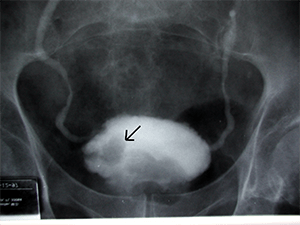

Медицинский термин «уретрография» используют для обозначения неинвазивного диагностического метода, направленного на исследование органов мочеполовой системы с применением рентгеноконтрастных средств и рентгеновского оборудования.

Процедура имеет высокую диагностическую ценность, поскольку позволяет определить состояние и строение анатомических структур мочевыделительной и половой системы. Благодаря ей можно выявить патологические состояния и новообразования различной природы на разных стадиях их развития, но главной её целью, как правило, является определение проходимости мочеиспускательного канала — уретры.

Методика предусматривает заполнение мочевыводящего канала контрастным веществом с последующим совершением рентгеновских снимков. Иногда процесс фиксируют на видео для получения более расширенных данных о состоянии канала. В зависимости от того, каким способом вводят контраст, выделяют две методики уретрографии, ознакомиться с особенностями, которых можно в нашей таблице ниже: